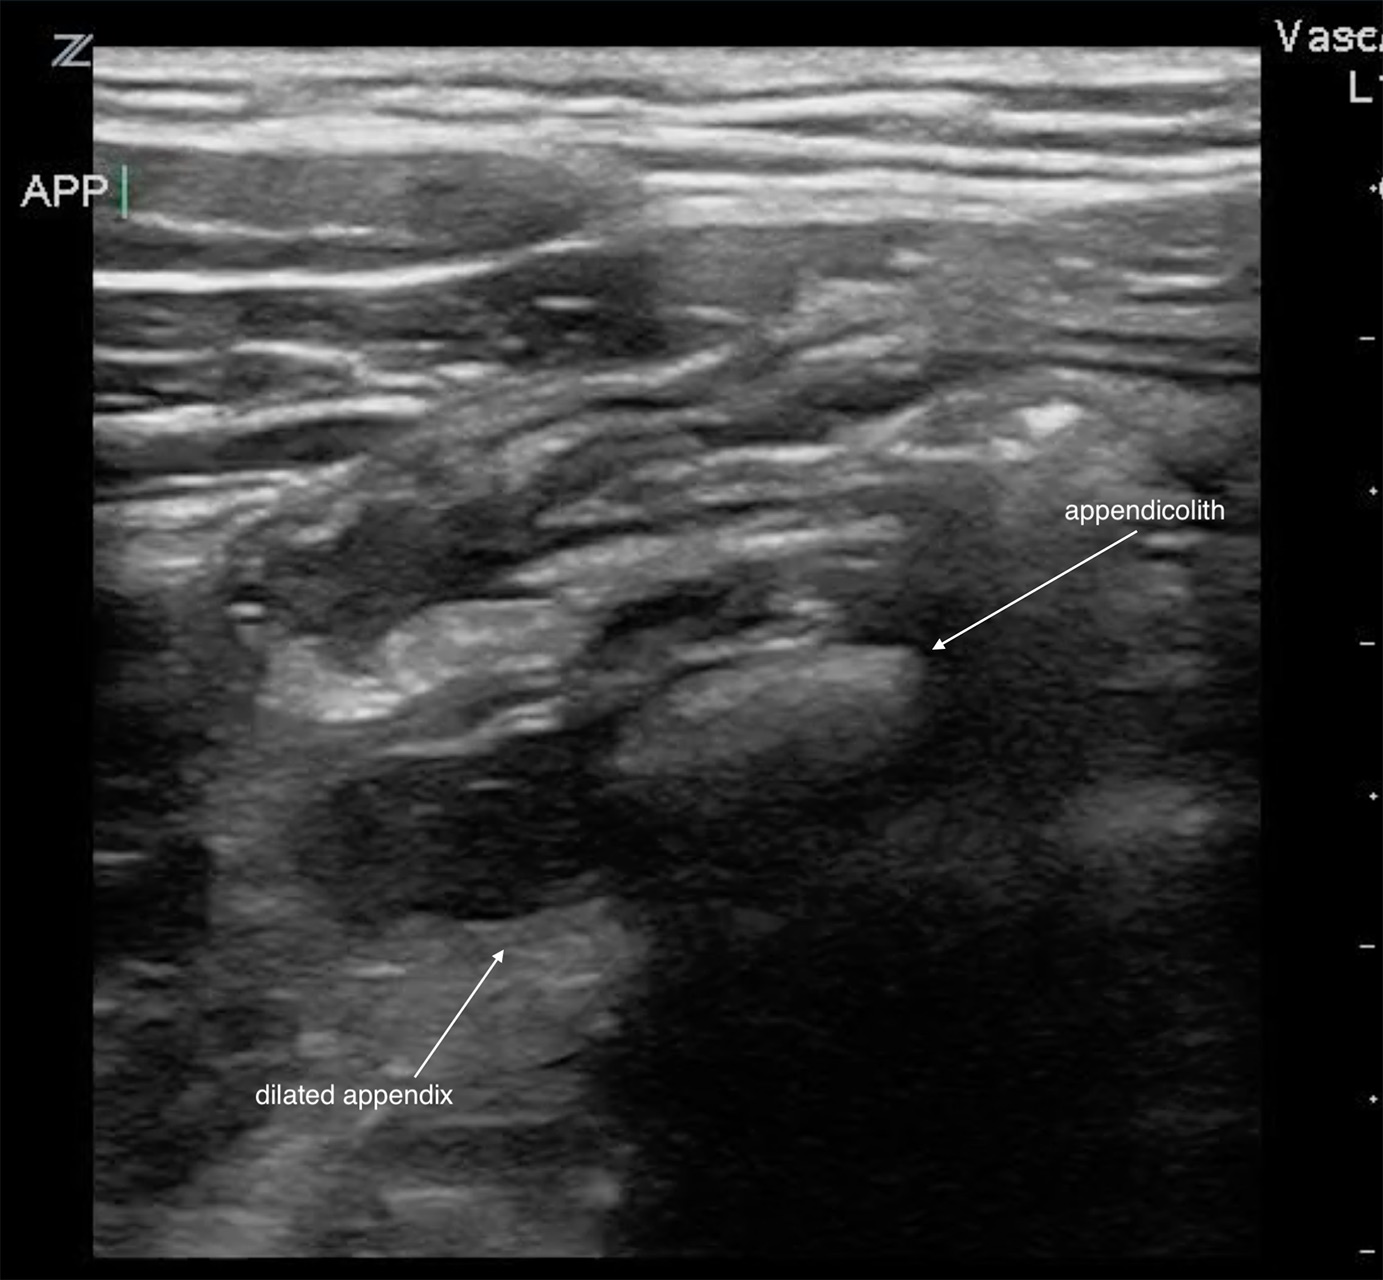

Other secondary sonographic findings (with varying sensitivities and specificities):

Presence of an appendicolith. Note that this may be seen in normal size appendix. When present, it is associated with an earlier and higher risk of perforation.12

Figure 6. Appendicolith in acute appendicitis.

Video 4. Appendicolith in acute appendicitis.